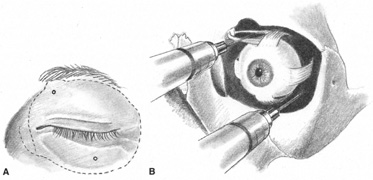

The motor supply of the superior, medial, and inferior rectus, the inferior oblique, and the levator palpebrae superioris is carried by the oculomotor nerve (Fig. 2). It also carries proprioceptive input from these muscles and parasympathetic fibers to the ciliary ganglion. As the oculomotor nerve enters the orbit through the superior orbital fissure, it splits into two divisions, superior and inferior. The superior division is smaller; it courses forward in the superolateral portion of the intraconal space, and turns medially toward the lateral aspect of the superior rectus muscle, where it divides into a network of small branches.49 The innervation of all extraocular muscles is multifocal, with nerve fibers extending distally and proximally between the muscle fibers, before ending at myoneural junctions.47 Some branches innervate the superior rectus, and others pass through it to enter the levator muscle through its inferior surface.

The trochlear nerve supplies motor fibers to the superior oblique muscle. It enters the orbit through the superior oblique fissure above the annulus of Zinn, along with the frontal and lacrimal branches of the ophthalmic division of the trigeminal nerve. It crosses the superior rectus origin above the levator and enters the superolateral surface of the superior oblique muscle.47

The abducens nerve enters the orbit through the superior orbital fissure, along with the oculomotor nerve. They are sometimes divided by a dense septum connecting the superior rectus origin to the superior rectus sheath.47 The abducens nerve enters the lateral rectus sheath just anterior to the annulus of Zinn, and first enters the lateral rectus muscle at the medial aspect of the junction of its posterior and medial thirds.47,50